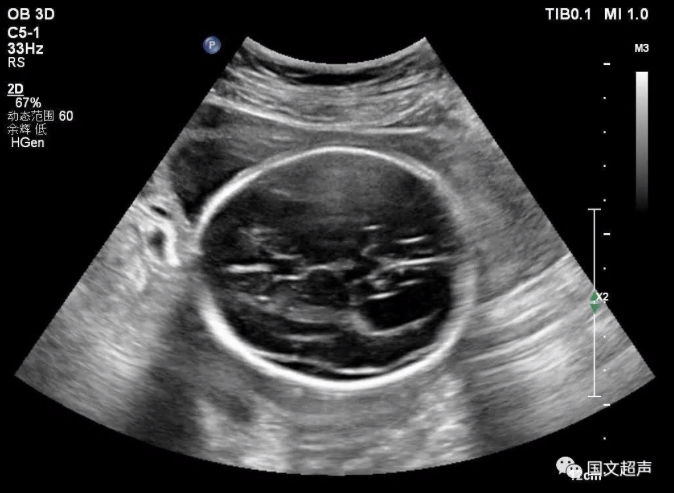

一.關于側腦室

側腦室后角寬度>10mm為腦室輕度擴張,而寬度>15mm時即可診斷腦積水,若側腦室后角寬度<10mm,則應考慮其為正常的超聲表現。

大部分輕度腦室擴張的胎兒預后良好,但約有20%的輕度側腦室擴張?zhí)嚎珊喜⒂腥旧w異常、其他顱內外異常等問題而出現智力或發(fā)育障礙,甚至在圍生期即死亡。